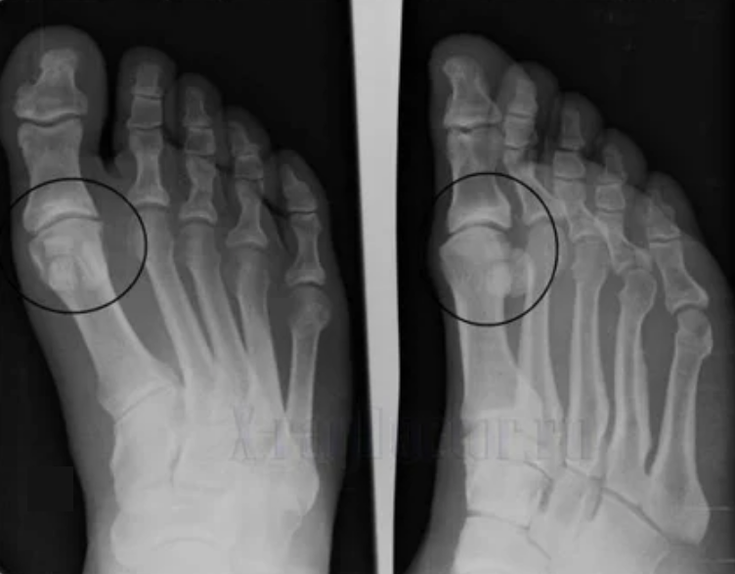

To make a diagnosis, rheumatologists examine the patient's symptoms and prescribe an X -Ray examination.Most of the time, radiography is used in 2 projections.The doctor examines the presence of dystrophic disorders in hyaline cartilage and bone joints.When the joint column is reduced, the bones are deformed or flattened, there are cystic formations on the surface of the cartilage, osteophytes are obvious signs of osteoarthritis.During inspection, arthrosis shows the instability of the joint: the axis of the limbs and subluxation is disturbed.

Often an X -Ray image is unable to provide complete information about the condition of the joint.Computer tomography is prescribed for a more thorough study and it is effective to examine bones.MRI is used more often to examine soft tissue.